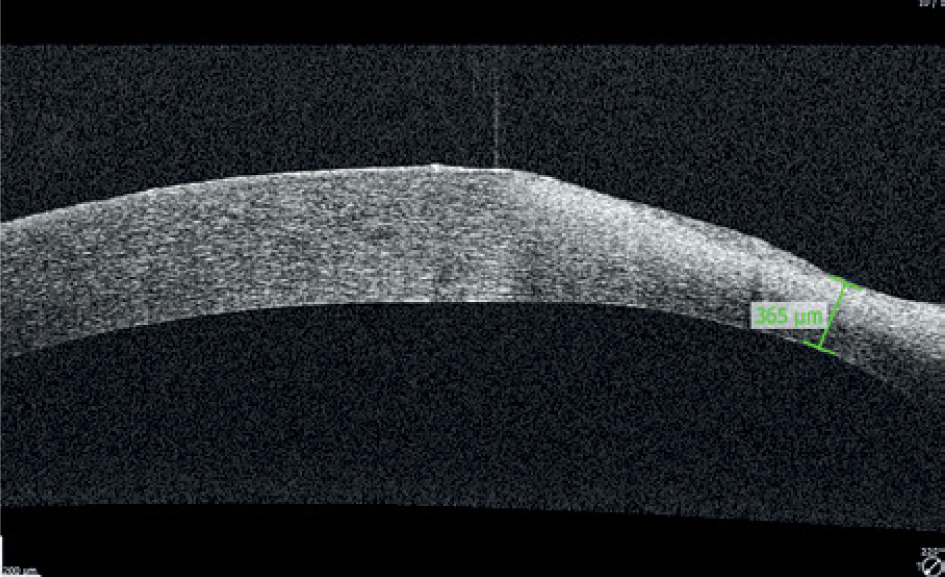

A 65-year-old woman, with a history of diabetes on oral medication for 5 years but no signs of diabetic retinopathy, was operated on for cortico-nuclear cataract by phacoemulsification with IOL PC with no perioperative complications. Her Snellen best corrected visual acuity (BCVA) was 0.6 preoperatively. The eye was quiet on the day of surgery; however, per records slight bilateral conjunctival redness with some secretion was noted 2 weeks before the operation. This condition was managed by prescription of Tobradex (tobramycin + dexamethasone) for 1 week. No BUT/fluorescein staining was performed at that time. Immediate postoperative BCVA was 0.5. The patient was discharged from the hospital with routine prescription of antibiotic-steroid drops 4 times a day and 0.1% diclofenac drops 4 times a day (Dicloabak, Laboratoires THEA, France). One week after the operation she presented to the emergency room complaining of foreign body sensation without any pain. Her BCVA was CF at 1 m. Slit lamp examination showed little perilimbal injection with horizontally oval corneal ulcer located centrally (Figure 1). On OCT decrease in thickness of the cornea corresponding to this ulcer was noted (Figure 2). The other eye showed signs of filamentary keratopathy (Figure 3). The serious nature of the complication was discussed with the patient. Diclofenac and steroid drops were stopped. Nonpreservative tears hourly and levofloxacin drops 3 times a day were prescribed. Successful healing of corneal ulcer was noted at subsequent follow-up visits at 1 week, 2 weeks and 1 month without any need for amniotic membrane transplantation. At the 1-month follow-up visit her BCVA was 0.4 and there was opacification at the anterior cornea and persistent filamentary debris (Figure 4). Further investigations revealed increased ESR and circulating autoantibodies SS-A, SS-B, Ro-52. In addition, the patient’s history was significant for mouth dryness and lack of smell for about 7 years. Subsequently, she has been diagnosed with Sjögren syndrome.